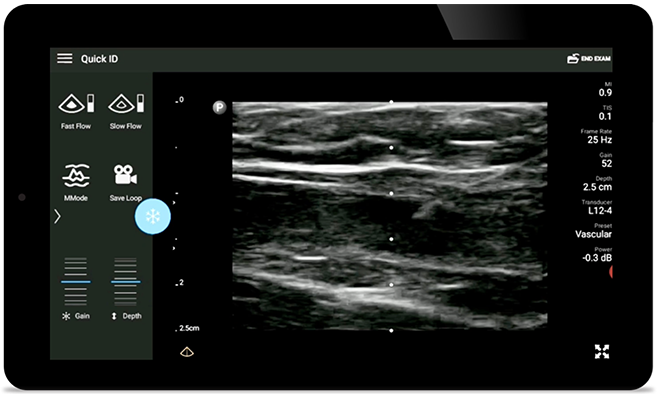

Decrease complications of CVC insertions

Real-time ultrasound guidance can improve the accuracy and safety of CVC insertions.

Lumify L12-4 broadband linear array transducer

• 12 to 4 MHz extended operating frequency range • Aperture size: 34mm • 2D, steerable color Doppler, M-mode, advanced XRES and multivariate harmonic imaging, SonoCT • High resolution imaging for shallow applications: soft tissue, vascular, superficial, musculoskeletal, and lung • Center line marker • USB-C transducer with replaceable cable